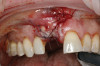

Prior to the initiation of the surgery, the surgical guide was tried in to confirm proper seating and stability (Figure 15). A flapless approach was not considered because the need for further bone grafting at the time of implant placement had been anticipated through the digital planning. A slightly palatal crestal incision was made, followed by two vertical incisions on the mesial and distal aspects of the edentulous site in order to preserve the papilla and avoid additional esthetic compromise to the anterior sextant. Next, a full-thickness flap was elevated to facilitate removal of the tenting screw and permit visualization of the buccal plate (Figure 16). A standard guided protocol was followed to place the implant, and its final position mirrored that of the digital plan. As predicted, the prosthetically driven implant position resulted in an insufficient buccal plate (Figure 17); therefore, additional guided bone regeneration was performed to reinforce the area and prevent future breakdown (Figure 18 and Figure 19). Making periosteal incisions could have compromised the blood supply to the flap, so instead, it was stretched in order to achieve tension free coronal advancement.31The flap was secured utilizing horizontal mattress sutures with additional supportive interrupted sutures to ensure primary closure (Figure 20). An immediate postoperative periapical radiograph (Figure 21) and CBCT scan (Figure 22) were taken, demonstrating a final implant position centered with the planned location of the gingival zenith.

(17.) Implant placed 1-mm distal to the midline of the edentulous space, corresponding with the planned location of the gingival zenith. Note the lack of sufficient bone buccal to the implant that necessitated further grafting.

Figure 17